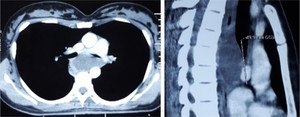

Bệnh viện Trung ương Quân đội 108 vừa cấp cứu thành công một bệnh nhân bị kén phế quản khá hiếm.